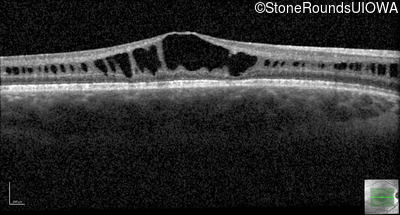

Optical Coherence Tomography - Right - 20/63 +1

Exemplar / OCT Stack

OCT Stack